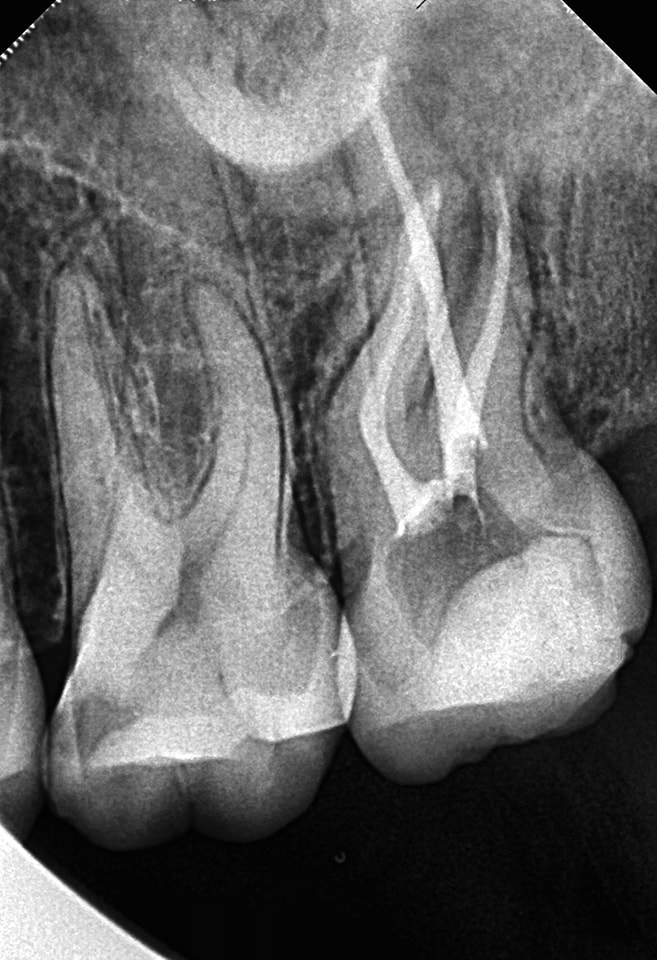

Obturation